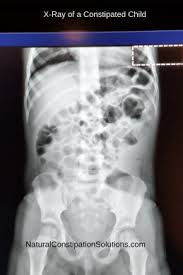

Pin On Alternatives To Miralax Natural Constipation Solutions